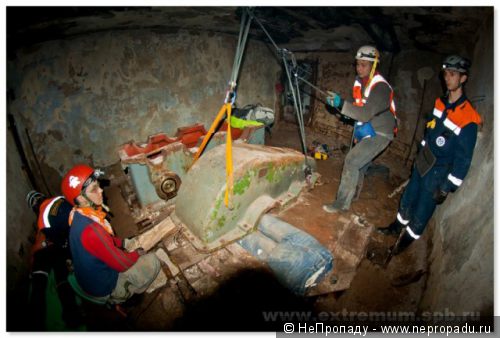

Раздел: Фотоэссе